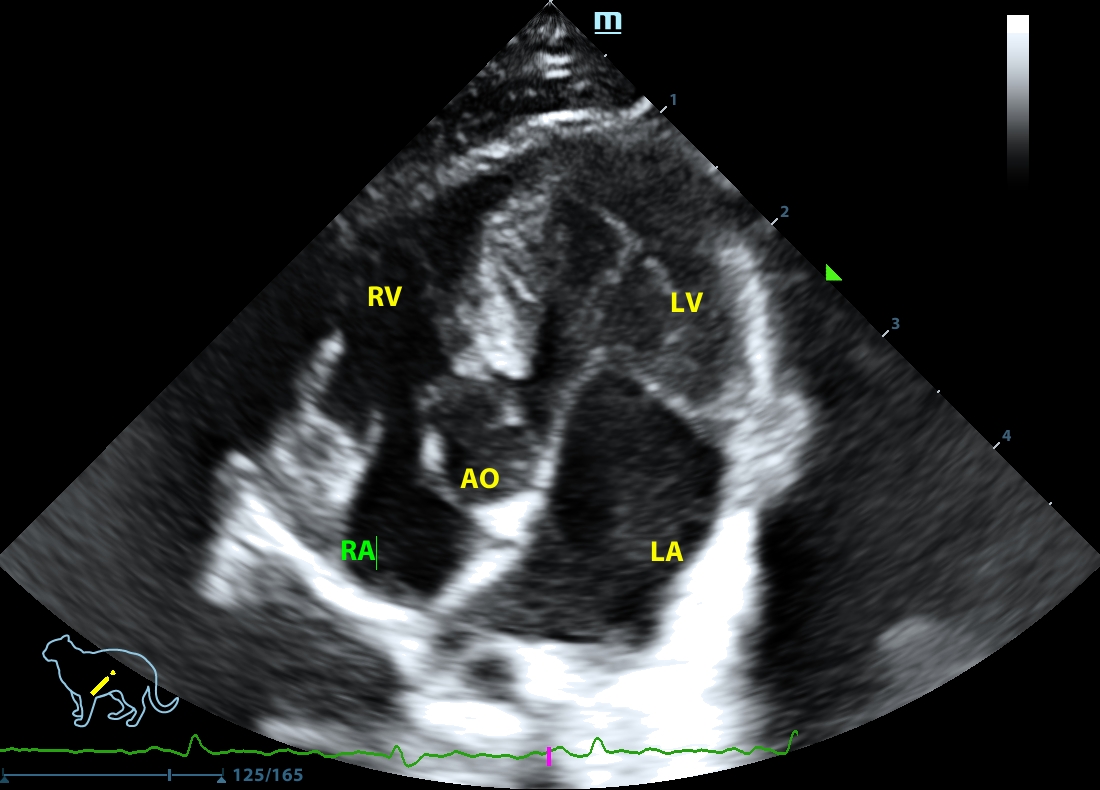

202505170045570152CARD.JPG